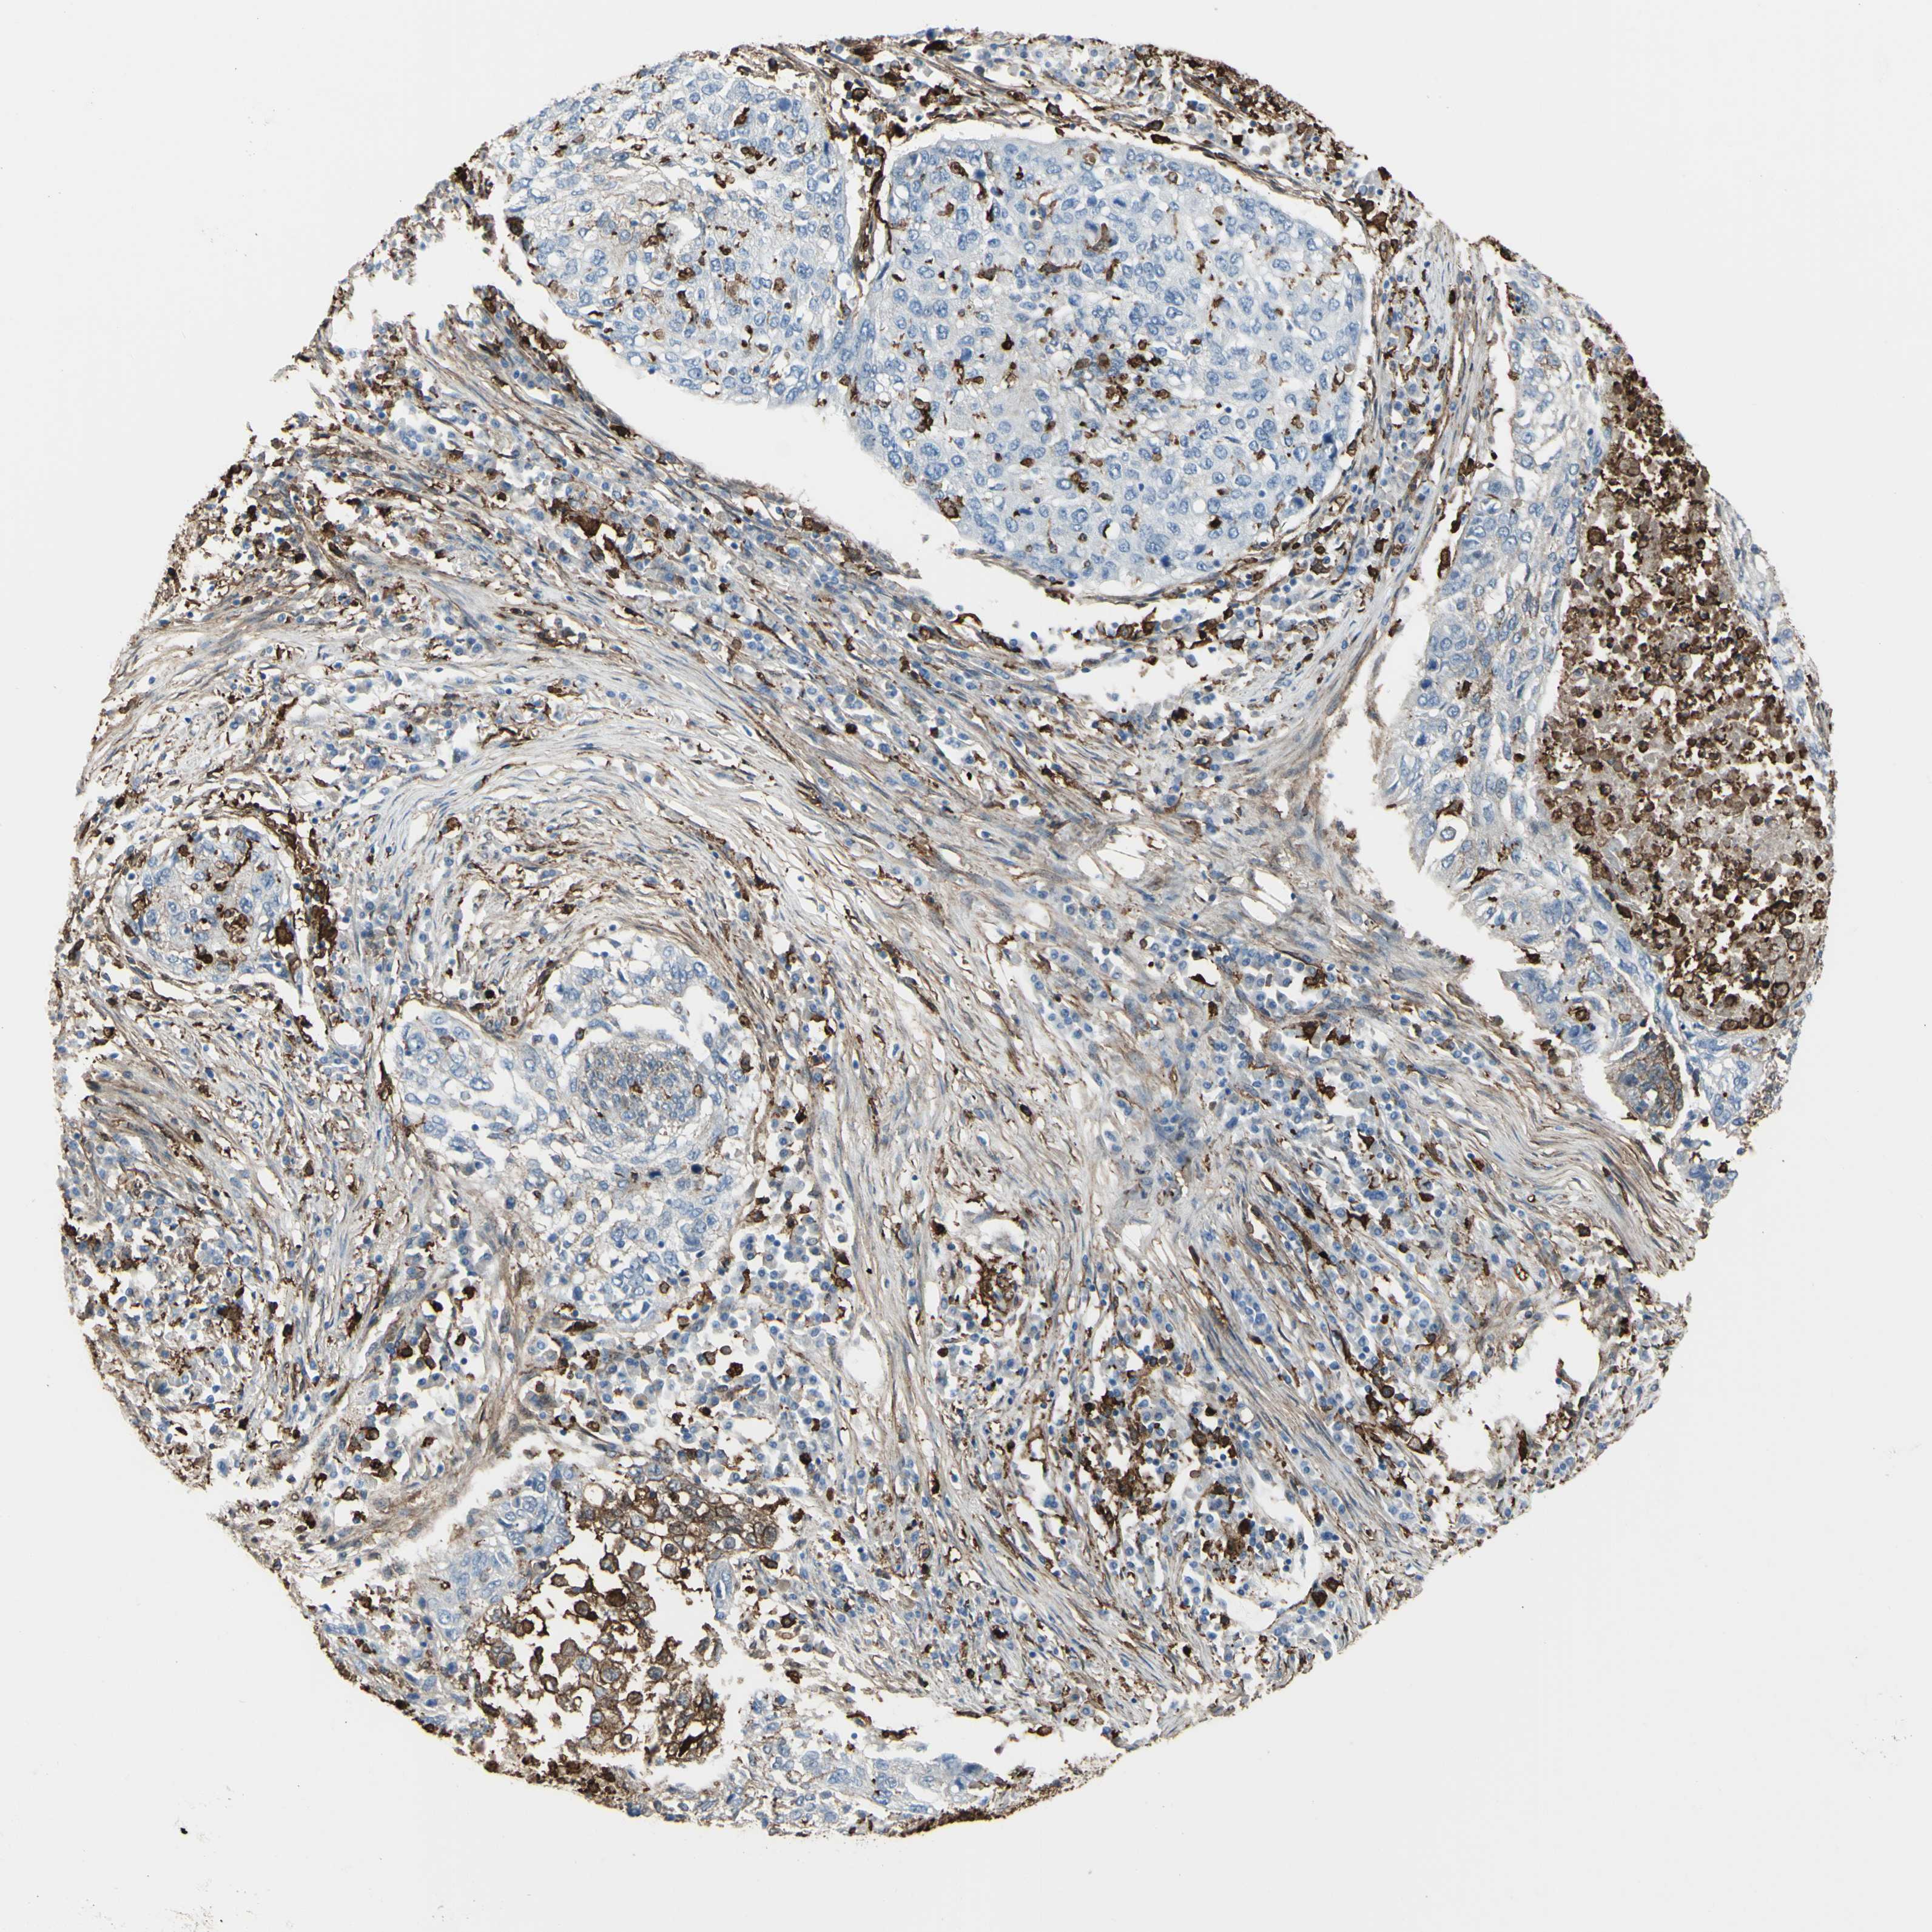

LUNG SQUAMOUS CELL CARCINOMA (TCGA) - Interactive survival scatter ploti

The Survival Scatter plot shows the clinical status (i.e. dead or alive) for all individuals in the patient cohort, based on the same data that underlies the corresponding Kaplan-Meier plots. Patients that are alive at last time for follow-up are shown in blue and patients who have died during the study are shown in red.

The x-axis shows the expression levels (FPKM) of the investigated gene in the tumor tissue at the time of diagnosis. The y-axis shows the follow-up time after diagnosis (years). Both axes are complimented with kernel density curves demonstrating the data density over the axes. The top density plot shows the expression levels (FPKM) distribution among dead (red) and alive patients (blue). The right density plot shows the data density of the survived years of dead patients with high and low expression levels respectively, stratified using the cutoff indicated by the vertical dashed line through the Survival Scatter plot. This cutoff is automatically defined based on the FPKM cutoff that minimizes the p-score. The cutoff can be changed by dragging the vertical line or by entering a cutoff value in the square labeled "Current cut-off".

Under the Survival Scatter plot the p-score landscape (black curve; left axis) is shown together with dead median separation (red curve; right axis). Dead median separation is the difference in median mRNA expression between patients who have died with high and low expression, respectively. It is calculated as follows: median FPKM expression of dead patients with high expression - median FPKM expression of dead patients with low expression. This is intended to aid the user in visually exploring custom cutoffs and the associated p-scores and dead median separation.

Individual patient data is displayed and can be filtered by clicking on one or more of the category buttons on the top of the page. Categories describing expression level and patient information include: high, low, alive, dead, female, male and tumor stages. The scale of the x-axis can be toggled between linear and log-scale by clicking on the "x log" button. Mouse-over function shows TCGA ID, patient information and mRNA expression (FPKM) for each patient.

& Survival analysisi

Kaplan-Meier plots summarize results from analysis of correlation between mRNA expression level and patient survival. Patients were divided based on level of expression into one of the two groups "low" (under cut off) or "high" (over cut off). X-axis shows time for survival (years) and y-axis shows the probability of survival, where 1.0 corresponds to 100 percent.

GSN is not prognostic in Lung Squamous Cell Carcinoma (TCGA)

Best expression cut offi

Based on the FPKM value of each gene, patients were classified into two groups and association between prognosis (survival) and gene expression (FPKM) was examined. The best expression cut-off refers the FPKM value that yields maximal difference with regard to survival between the two groups at the lowest log-rank P-value. Best expression cut-off was selected based on survival analysis .

When clicking on this number, the vertical dashed line indicating cut-off, the interactive survival plot, and the Kaplan-Meier curve will be adjusted to show results based on the best expression cut-off.

: 160.01

P scorei

Log-rank P value for Kaplan-Meier plot showing results from analysis of correlation between mRNA expression level and patient survival.

N/A

TCGA RNA samplesi

RNA-seq data is reported as average FPKM (number Fragments Per Kilobase of exon per Million reads), generated by the The Cancer Genome Atlas (TCGA) .

Normal distribution across the dataset is visualized with box plots, shown as median and 25th and 75th percentiles. Points are displayed as outliers if they are above or below 1.5 times the interquartile range. FPKM values of the individual samples are presented next to the box plot.

Average pTPM 267.8

Number of samples 489